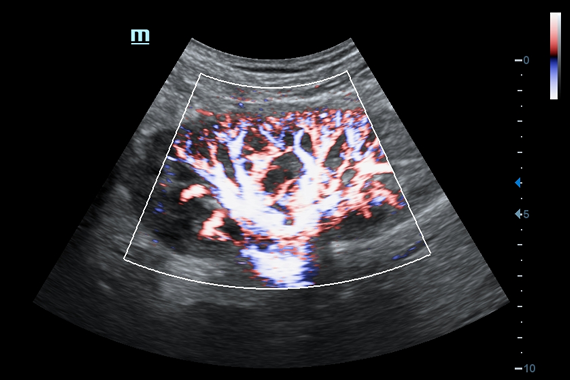

• HR Flow - режим отображения кровотока с высоким временным и пространственным разрешением для точной и однородной визуализации сосудов, в том числе самых мелких.